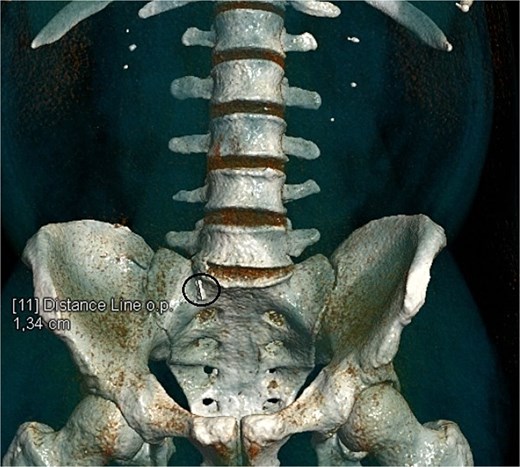

CT scan reconstruction—cluster of stones sizes, respectively, 5.2 mm, 3.2 mm, 2.8 mm—13.4 mm combined in the right distal ureter.

As a result of the CT scan, the diagnosis of spontaneous steinstrasse type 2 with complete obstruction of the right ureter was established. The patient was referred to the urology clinic where a decision was made to perform ESWL. In the following days the patient remained symptomatic with persistent hydronephrosis. Therefore it was decided that the next therapeutic step will be ureteroscopic stone disintegration. The procedure was successful and in the subsequent months, imaging studies showed no signs of hydronephrosis and the patient reported no symptoms.

The term “steinstrasse” was first used by Egbert Schmiedt and Christian Chaussy, in the 1980s to denote the accumulation of calculi in the ureter resulting from the performance of ESWL [1]. SS is observed in 15% of patients who have undergone extracorporeal shock wave lithotripsy [3]. The classification of steinstrasse includes three types (Table 3) [5]. In our case the patient suffered from type 2 steinstrasse with a leading fragment of 5.2 mm and tail formed by smaller fragments.